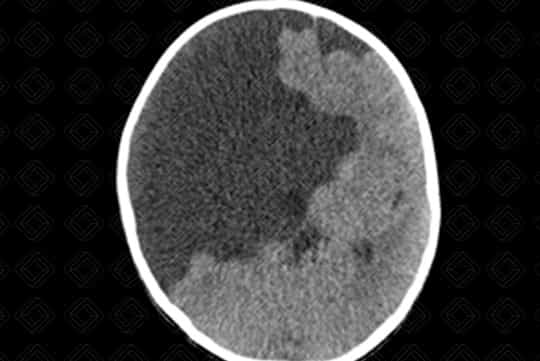

Descrição da lesão: Tomografia computadorizada do crânio com reformatações nos planos coronal e axial. Fenda preenchida por densidade liquórica na região parietal direita, caracterizando esquizencefalia de "lábios abertos" (primeira imagem).

Esquizencefalia : Trata-se de fenda transcortical delimitada por substância cinzenta. Elas podem ser de lábio aberto (grande defeito) ou lábio fechado (pequeno defeito). Até metade das esquizencefalias são bilaterais. Quando bilaterais, até cerca de 60% das esquizencefalias são de "lábios abertos" de ambos os lados.

• Tomografia computadorizada do crânio: N a tomografia de crânio é de fácil visualização o defeito e sua comunicação com o sistema ventricular. Vale lembrar que a ausência de septo pelúcido está presente em quase todos os casos;